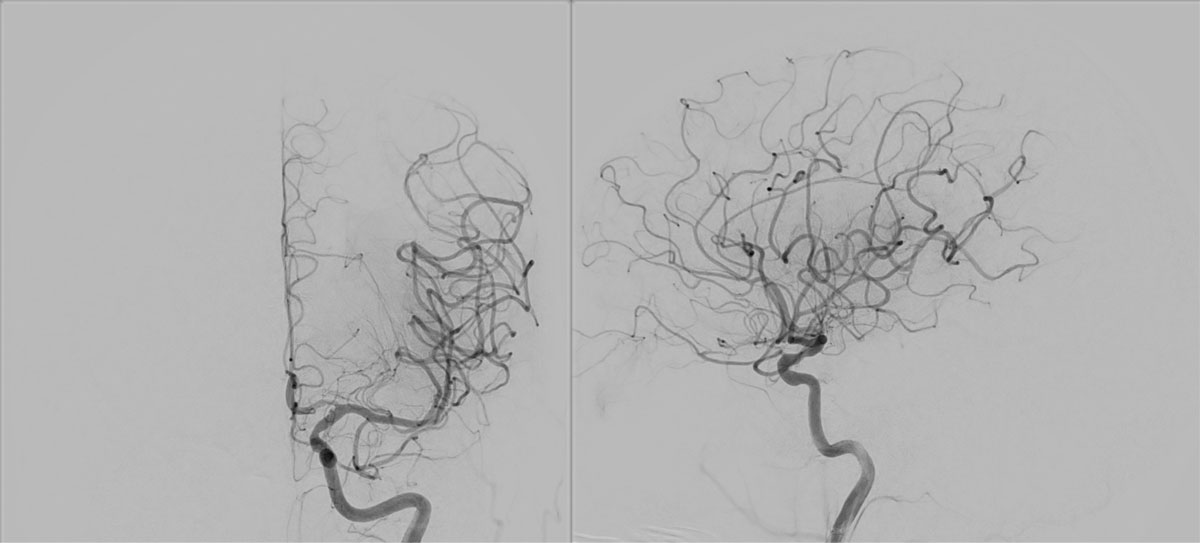

ICA-M1 intracranial dissection EVT

This clinical case presents a 28-year-old female patient presenting with a wake-up stroke, managed with endovascular treatment.

VASO-CT post

6 months DSA follow up